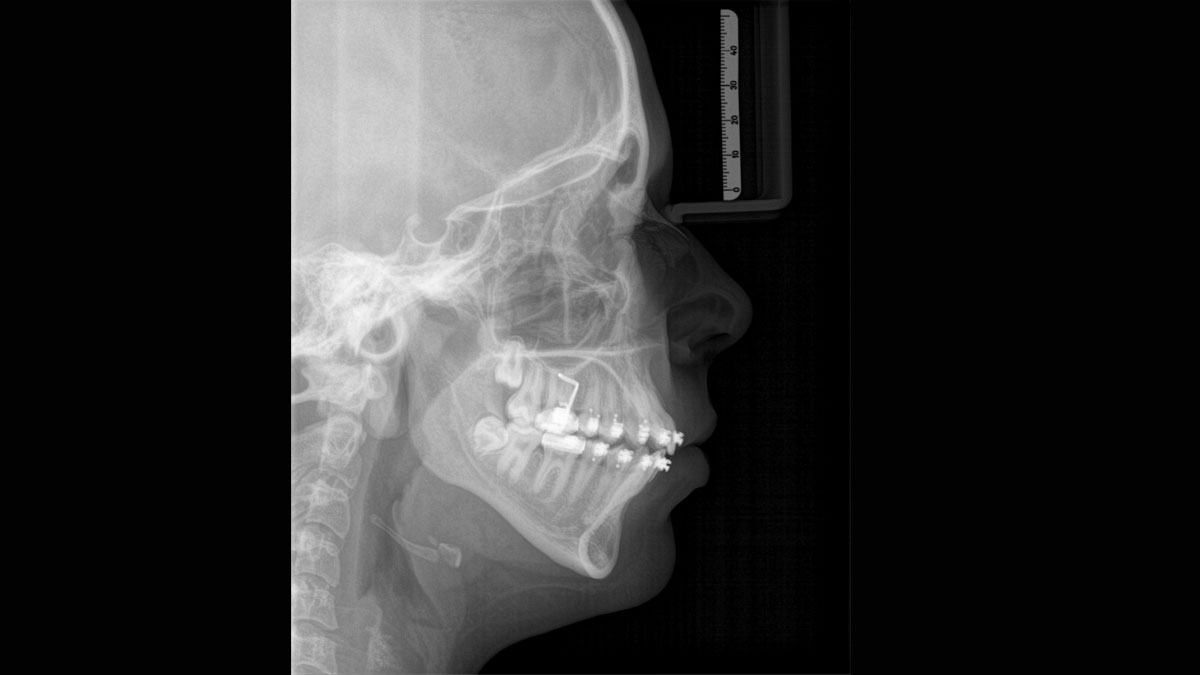

Für außergewöhnliche Panoramabilder mit hoher Schärfe. Sie können einen optionalen rechten oder linken Fernröntgenausleger wählen, der jederzeit nachgerüstet werden kann.

Dank des optimierten Low Dose Modus mit dediziertem Filter wird die Abbildung dichter Strukturen wie etwa Knochen bei stark reduzierter Dosis ermöglicht. Das macht Intelligent Low Dose zu einer attraktiven und effizienten Option bei vielen klinischen Fällen. Ob in der Kieferorthopädie oder Implantologie – mit den Dentsply Sirona Lösungen finden Sie für jeden Fall die optimale Einstellung.